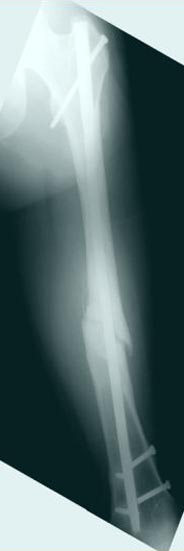

Из истории болезни: два года назад проперирован по поводу 3А открытого перелома бедра, травма на работе в результате "стена упала на него".Сопутствующая травма: Закрытая травма черепа, перелом голеностопного сустава (прооперериван) и перелом плеча (консервативное лечение)

Лечение бедра - ургентное оперативное лечение антеградным с минимально рассверливанием, фиксацией с минимальным диаметром штифта и плюс irrigation and debridment и с закрытием поперечной до 10 см раны на уровне перелома в день поступления.

Снимки представлены: 1 мес; 3 мес; 1 год; 2 года, предоперационные и ротационная КТ грамма

Деформация:

Вальгус- 17 градусов

Рекурватум 5 градусов

Укорочение 2.5см

Ротационно 22 градусов внутренная

Смещение диафиза по поперечнику 75%